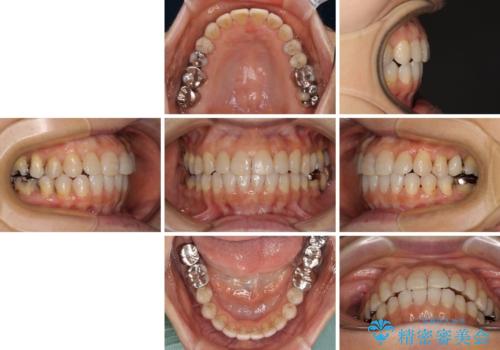

前歯の突出感と上下の隙間 インビザラインによる矯正治療

- 前歯の上下スペースと前歯の隙間を気にして来院された患者様です。

インビザラインにより上下の前歯の隙間を閉じながら、IPRを用いて口元の突出感を合わせて改善していくこととしました。

上下の隙間に舌が入り込むことが、すきっ歯やオープンバイトの原因であったため、舌の筋肉のトレーニングも並行して行い、後戻りの抑制を図りました。